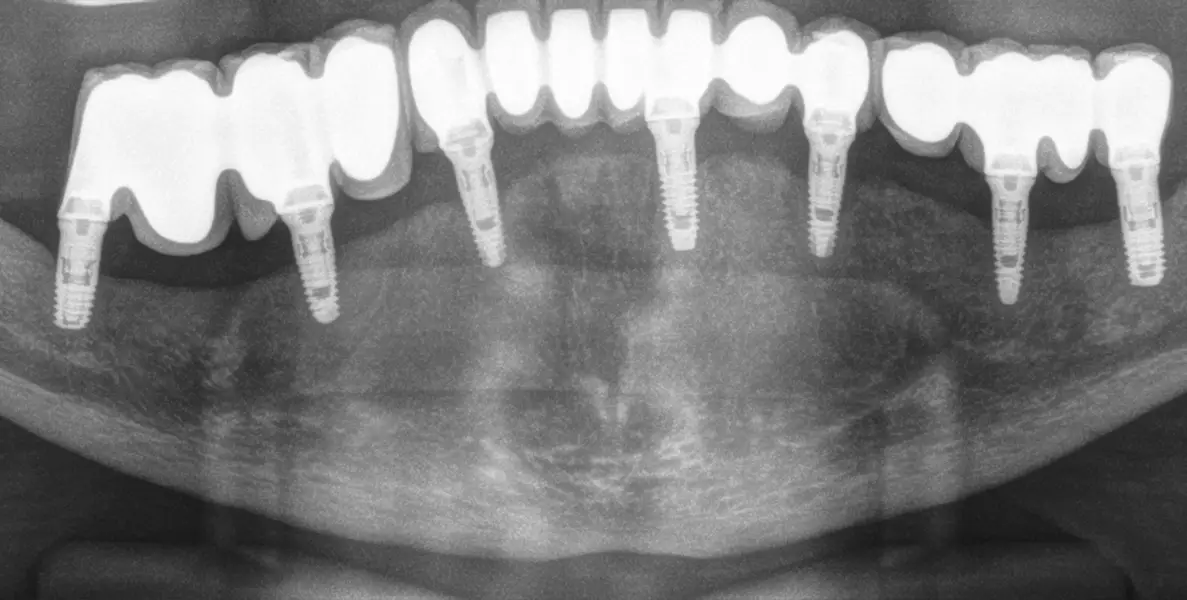

Figura 23. Radiografía con la prótesis final en el momento de su colocación, 6 meses de la carga inicial. Como vemos la prótesis final se divide en tres sectores para lograr un mejor comportamiento biomecánico del conjunto.

Figura 28. Radiografía panorámica de control dos años después, observándose la estabilidad lograda y el mantenimiento del hueso crestal en todos los implantes.